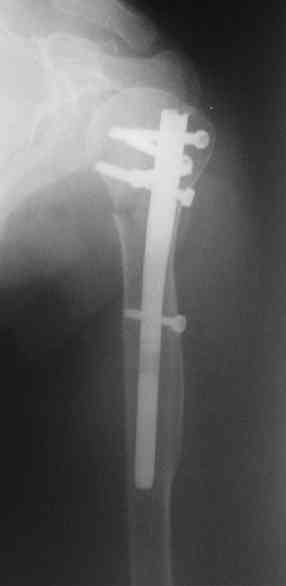

I am attaching the radiographs of the mother of a doctor. She has chronic renal failure for >10 years, diabetes mellitus and coronary artery disease. Age 62. She was offered the options of non-surgical management in a sling and surgery with a locking plate. She was given Tramadol for pain relief. Five days after injury, patient requested surgery, because of pain, inability to move without pain.

The reduction is not perfect. The patient is very small made, and it was difficult to bring the plate proximally without impingement in abduction.

Pain relief after surgery was early and sustained.

I agree that this reduction is not perfect. The gap may later result with nonunion. Such or even better reduction can be reached without site

opening as you mentioned. Locking plates are positioned as less invasive, why so long incision was - even longer than plate?

Pls compare wound size visible at x-rays of your example with ones after typical closed nailing of the proximal humerus.